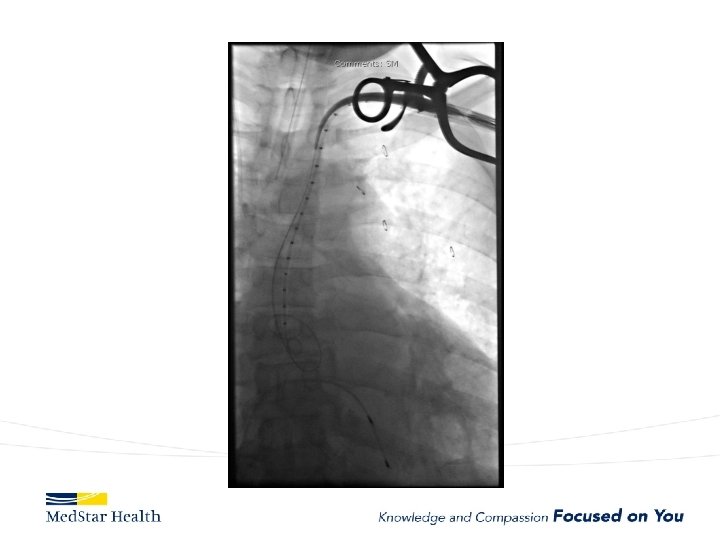

How Do We Treat • Open repair-unacceptable morbidity and mortality • TEVAR – Improved morbidity and mortality – Coverage of primary entry tear – Additional coverage?

Aneurysms • Descending – Obvious first choice assuming anatomically favorable • Ascending – IDE, Off label in high risk patient • Arch – Available in Europe, Under Trial in US • Thoraco – Available in Europe, Under Trial in US

Ascending Aorta • Currently off label unless in IDE • Challenges – Devices too long or too small for ascending – More complex terrain • Entire cardiac output • Valve/coronaries below • Inomminate above. – New Commercial Devices now available (shorter/tapered)

Current experience with ascending TEVAR JTCVS 2017 Nov 22, Roselli et al. 2006 to 2016 39 patients very high risk for open surgery – A dissection (12, 31%), – intramural hematoma (2, 5%), – pseudoaneurysm (22, 56%), – chronic dissection suture line entry tear (3, 8%). TEVAR in 36 Operative mortality 13%; 5 deaths all in Type A dissections Other complications: – stroke in 4 patients (10%), myocardial infarction in 2 patients (5%), tracheostomy in 2 patients (5%), and dialysis in 2 patients (5%).